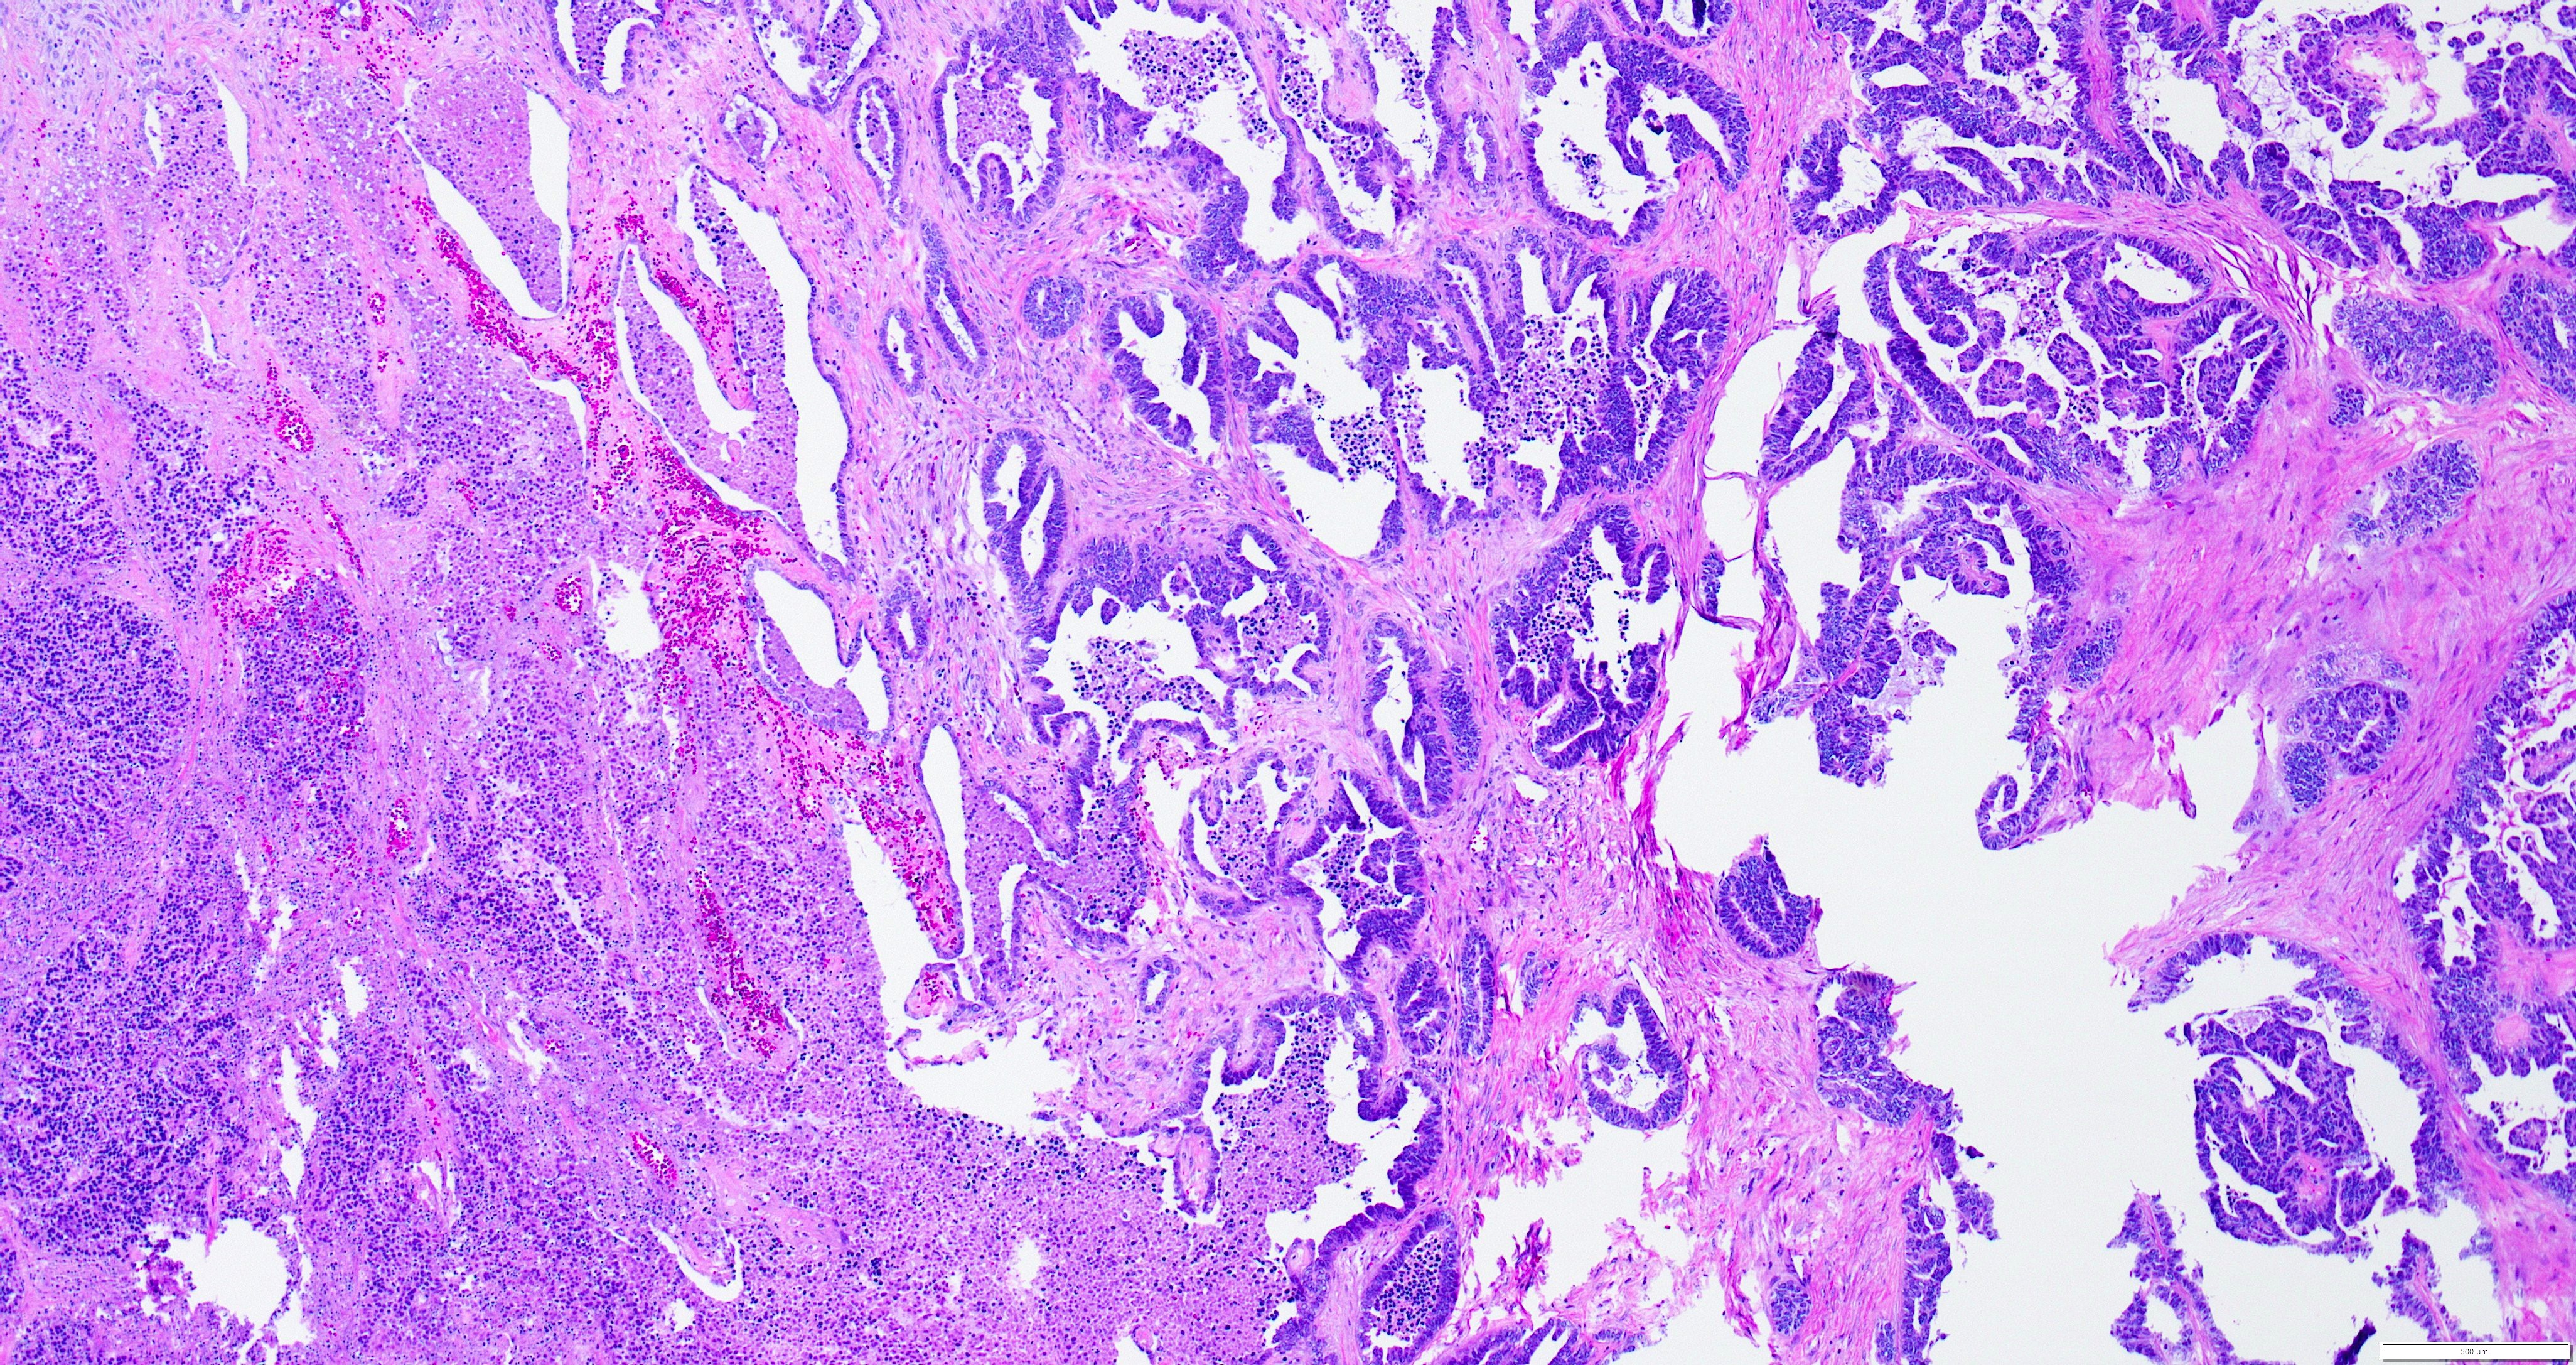

- Variety of histologic patterns that may be present within the same tumor

- Most frequently small tubules with ductal / glandular growth

- Papillary, solid growth, trabecular, retiform, sex cord-like, sieve-like, glomeruloid and spindle cell areas have all been described

- Luminal eosinophilic secretions are characteristic but not always identified

- Tumor cells can be flattened, cuboidal or columnar with mild to moderate cytological atypia

- Clear cell features can be seen but are less common

- High grade cytological atypia is usually not a predominant feature

- Nuclei show vesicular chromatin and nuclear grooves

- Sarcomatoid transformation has been seen in rare instances

- Squamous, ciliated or mucinous differentiation (metaplasia) are not present and there are no associated mesonephric remnants (J Clin Med 2021;10:698)

Microscopic (histologic) images

Contributed by Daniel Graham, M.D., Adele Wong, M.B., B.Ch., B.A.O. and Lucy Ma, M.D.